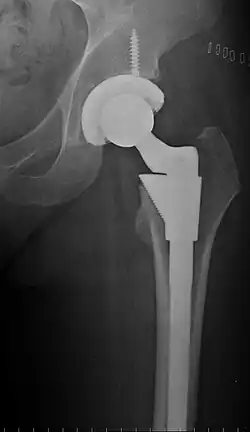

An X-ray showing a left hip (right of image) that has been replaced, with the ball of this ball-and-socket joint replaced by a metal head that is set in the femur and the socket replaced by a cup

Hip replacement is a surgical procedure in which the hip joint is replaced by a prosthetic implant, that is, a hip prosthesis.[1] Hip replacement surgery can be performed as a total replacement or a hemi/semi(half) replacement. Such joint replacement orthopaedic surgery is generally conducted to relieve arthritis pain or in some hip fractures. A total hip replacement (total hip arthroplasty) consists of replacing both the acetabulum and the femoral head while hemiarthroplasty generally only replaces the femoral head. Hip replacement is one of the most common orthopaedic operations, though patient satisfaction varies widely between different techniques and implants.[2] Approximately 58% of total hip replacements are estimated to last 25 years.[3] The average cost of a total hip replacement in 2012 was $40,364 in the United States (€37,307.44 in euros), and about $7,700 to $12,000 in most European countries. NOTE: In euros, that is from €7,116.92 to €11,091.30 euros.[4]